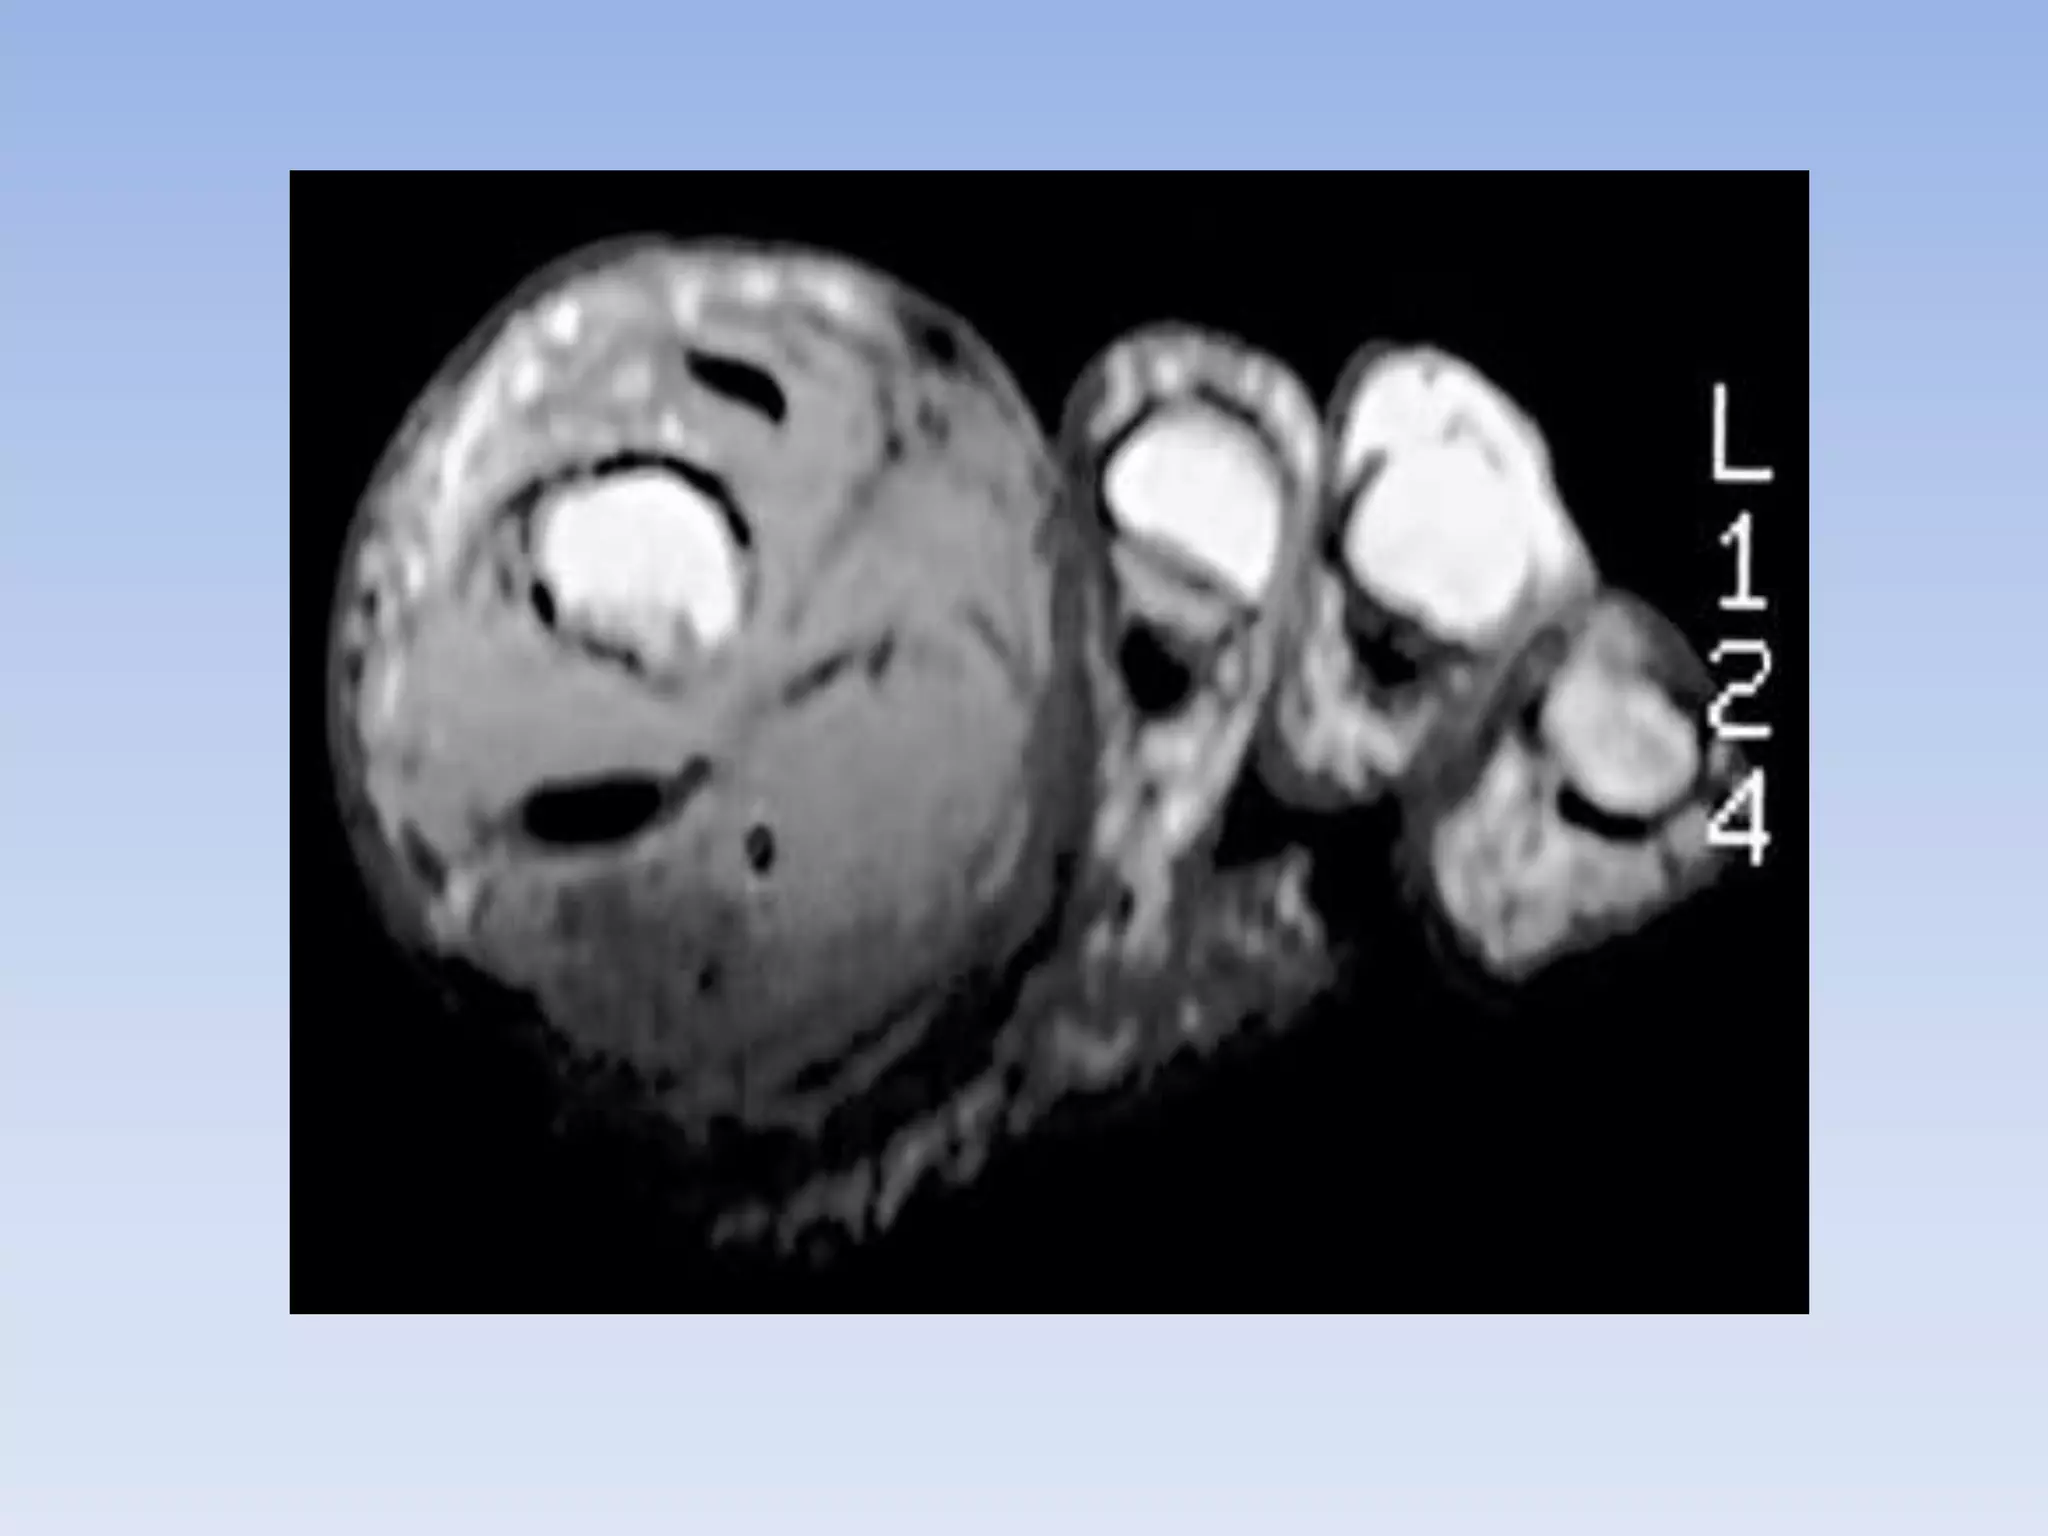

• Diffuse PVNS affects predominantly

large joints, with the knee being the

most common (66-80%).

Epidemiology • DiffusePVNS affects predominantly large joints, with the knee being the most common (66-80%). • The hip, ankle, shoulder, and elbow follow in descending frequency.